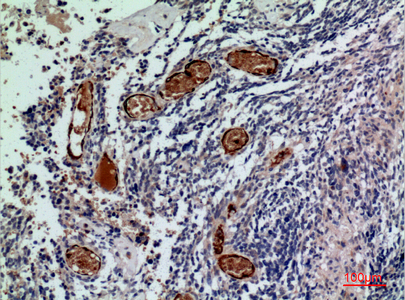

Immunohistochemistry analysis of paraffin-embedded Human liver using CD241 antibody.High-pressure and temperature Sodium Citrate pH 6.0 was used for antigen retrieval.

Immunohistochemistry analysis of paraffin-embedded Human liver using CD241 antibody. High-pressure and temperature Sodium Citrate pH 6.0 was used for antigen retrieval.